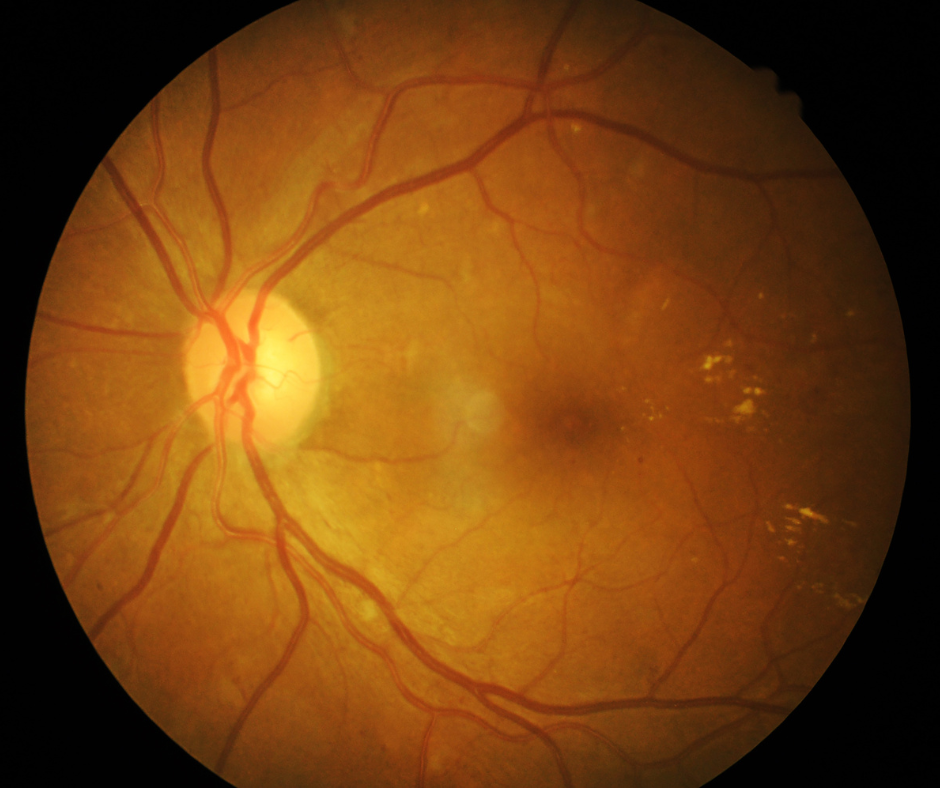

Diabetisches Makulaödem

Die diabetische Retinopathie (eine Netzhautveränderung) ist eine häufige Begleiterscheinung bei Diabetes mellitus. Das diabetische Makulaödem ist eine Verdickung der Netzhaut an der Stelle des schärfsten Sehens und ist die häufigste Ursache für den Sehverlust.

Glaukom - Grüner Star

Der Begriff Glaukom oder Grüner Star umfasst verschiedene Augenerkrankungen, bei denen der Sehnerv geschädigt wird. Der Augeninnendruck ist dabei oft erhöht.